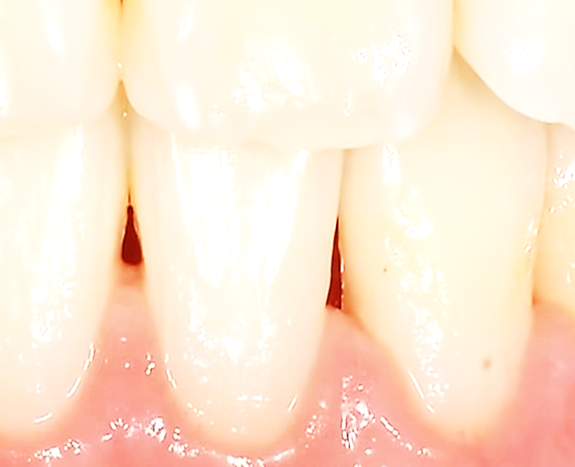

스케일링 후에 치아 사이 공간 ‘블랙 트라이앵글’이 보이기도 하는데 이것은 그동안 잇몸병이 진행되어 부었던 것이 가라앉으면서 생긴 흔적입니다.